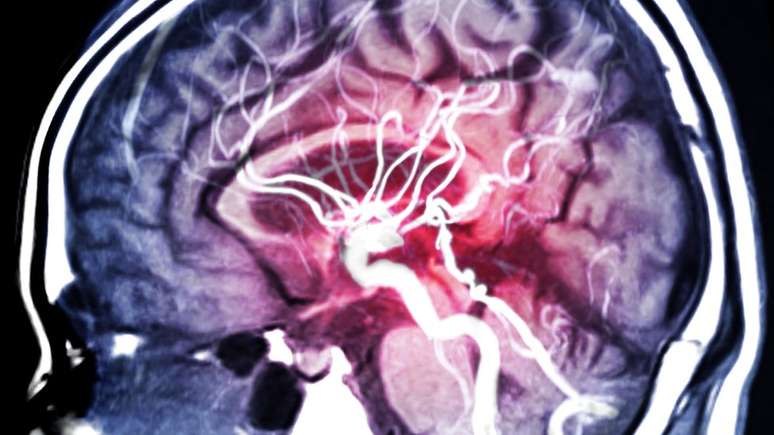

'É preciso imaginar o sistema de circulação (de sangue) da cabeça como uma árvore que tem um tronco — uma grande artéria — que se divide em galhos cada vez menores e tão minúsculos que nem temos nomes para eles', explica a neurologista Cristina Koppel

Foto: Getty Images / BBC News Brasil

"É preciso imaginar o sistema de circulação (de sangue) da cabeça como uma árvore que tem um tronco — uma grande artéria — que se divide em galhos cada vez menores e tão minúsculos que nem temos nomes para eles", explica Koppel.

"O coágulo, que pode ter se formado no coração ou nas artérias carótidas (artérias principais do pescoço), viaja por aquele sistema que vai se estreitando cada vez mais, bloqueando os vasos sanguíneos que alimentam partes do cérebro."

Um infarto silencioso só pode ser confirmado com ressonância magnética ou tomografia computadorizada